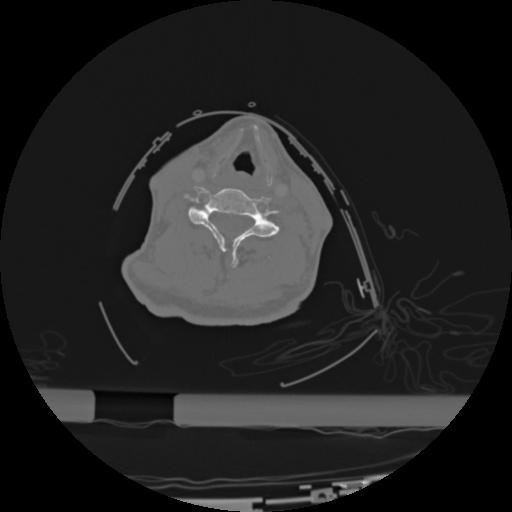

22 ANGIO,CE,Vol,0.5,ANGIO,,